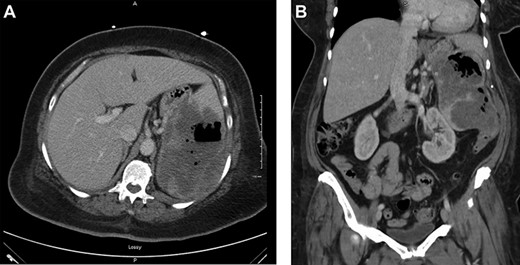

(a) Axial view of CT scan with intravenous contrast showed gastrocolic fistula. (b) Coronal view of contrast-enhanced abdominal CT scan. Large splenic mass fistulating into stomach and colon

resuscitated with 4 units of packed red blood cell. Upper endoscopy was suspicious for a large paraesophageal hiatal hernia with necrotic mucosa and adherent clot versus penetrating proximal gastric ulcer (Fig. 1) as a possible source of upper gastrointestinal bleeding. Computed tomography showed a largeheterogeneous mass occupying the spleen with air suspicious for splenic abscess versus large mass perforating stomach and colon (Fig. 2). She underwent exploratory laparotomy, en bloc partial gastrectomy with splenectomy and partial left colon resection with colostomy. GSF was observed with the greater curvature of the stomach and a splenocolonic fistula was observed with the splenic flexure of the colon (Fig. 3). There was tumor